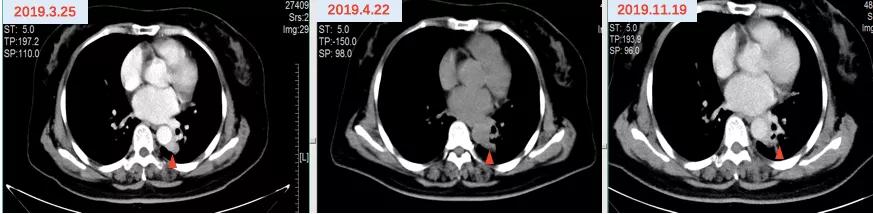

2019年2月26日因“活动后气促”于福建省东山县医院查胸部CTA示:左肺癌及化疗后改变,双肺下叶少许炎性灶,纵隔内及双肺门淋巴结肿大,肝内低密度灶,考虑转移灶?左右肺动脉局部及其部分分支充盈缺损,考虑癌栓形成。分子病理(ctDNA,ddPCR)EGFR T790M 0.89%。2019年2月28日开始口服“奥希替尼80mg qd”靶向治疗,并予低分子肝素抗凝治疗。2019年3月26日复查提示肺动脉瘤栓较前好转,左肺病灶较前略增大。(图6)

因考虑左肺病灶较前略增大,患者继续口服“奥希替尼80mg qd”靶向治疗,并于2019年3月26日开始联合“长春瑞滨40mg d1,3,5(口服3周停1周)”节拍化疗,定期复查疗效评价SD,PFS接近12个月。(图7)

图6 奥希替尼治疗前后影像资料

图7 “奥希替尼+长春瑞滨”治疗前后影像资料